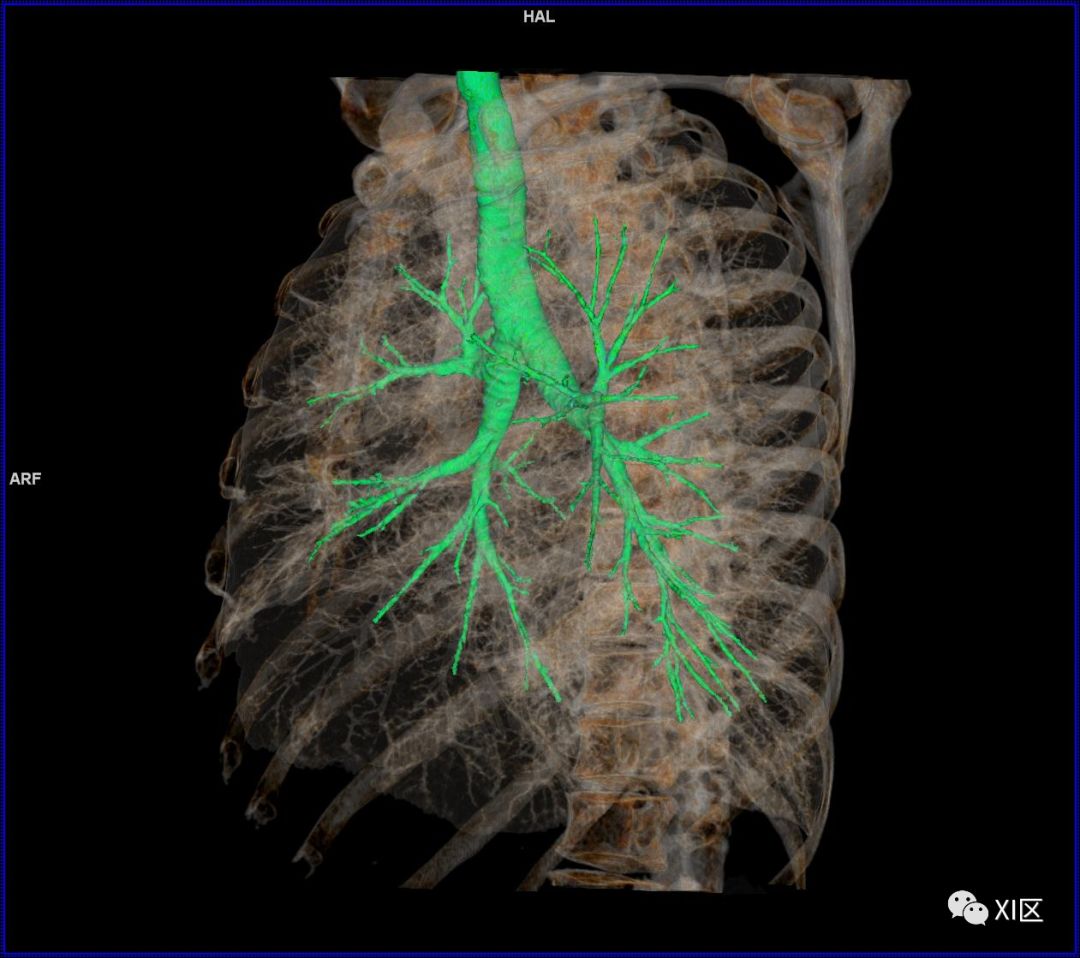

前后位,双侧位,后前位显示气道肺与胸部骨骼的关系

气管支气管树与两肺融合显示